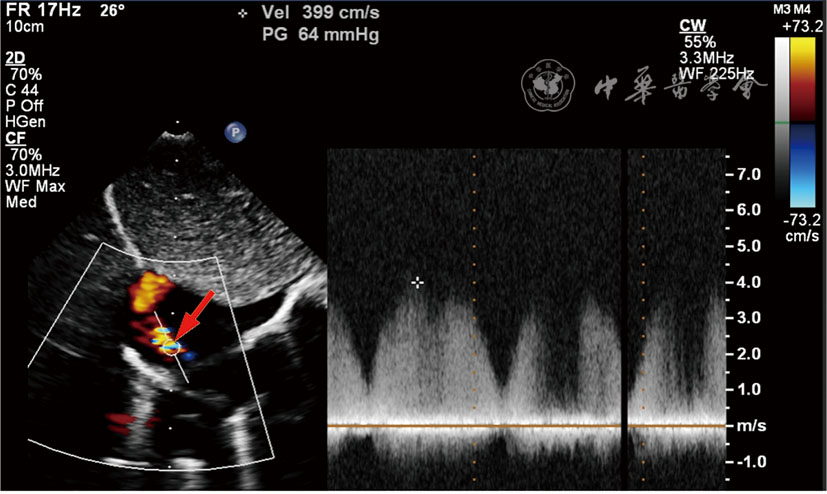

图2 冠状动脉右心房瘘超声图像。左图为彩色多普勒超声剑突下切面(箭头所示为瘘口);右图为连续多普勒测量瘘口血流速度约399 cm/s,压差约64 mmHg(1 mmHg=0.133 kPa)